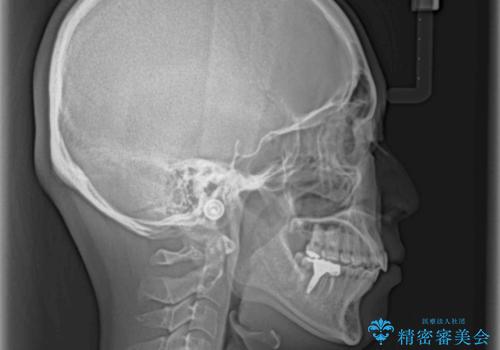

インプラント治療とインビザライン矯正治療 総合歯科治療

- 口の閉じにくさと割れてしまった奥歯を気にして来院された患者様です。

IPR(歯と歯の間を削る)と歯列全体の後方移動によって口元が引っ込むように設計し、インビザラインにより治療を行うこととしました。

割れてしまった奥歯は抜歯し、矯正治療中の良いタイミングでインプラントを埋入することとしました。

インプラントは、治療期間を短くすることが可能な、ストローマン社のSLActiveを使用することとしました。

上下正中がずれていたため、抜歯による矯正治療も検討しましたが、口元がそれほど突出していなかったため、非抜歯にて矯正することになりました。

その結果正中のズレは残りましたが、口を閉じたときの感覚や奥歯の咬み合わせには全く問題なく、患者様には大変満足していただきました。